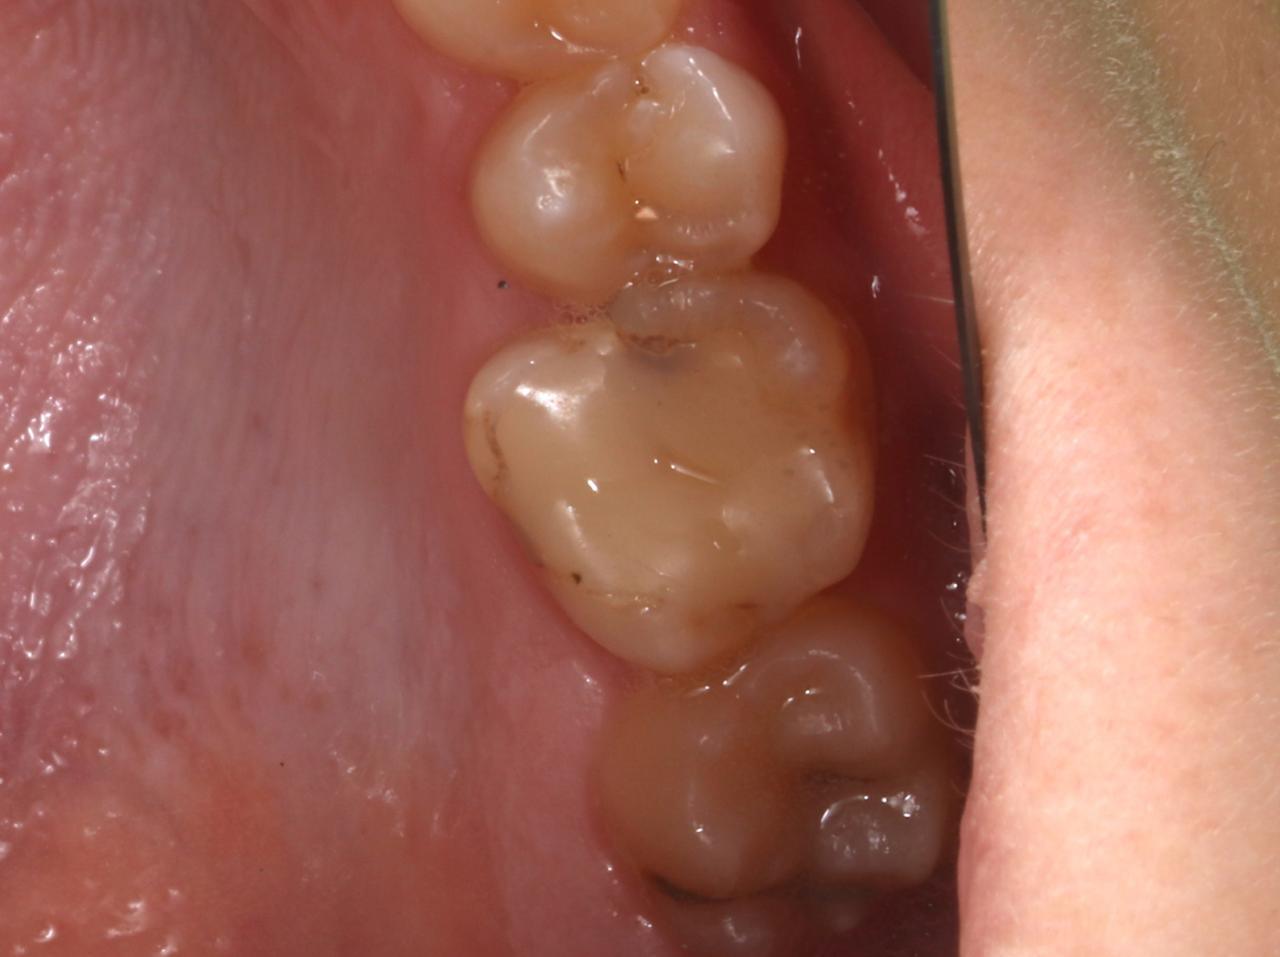

Fase III (Cárie dentária na dentina)

Quando a lesão de cárie já passa à fase III, significa que já há uma invasão de uma zona mais interna do dente, a camada de dentina, que protege a polpa dentária. Devido à proximidade ao centro do dente (polpa dentária) pode haver uma maior sensibilidade ao frio ou a comer alimentos açúcarados ou até mesmo uma sensação de dor e, por isso, é urgente o seu tratamento para evitar um avanço da lesão de cárie dentária.